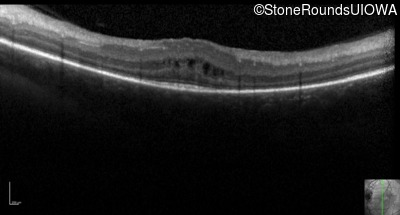

Optical Coherence Tomography - Left - 20/50 -3

Exemplar / OCT Stack